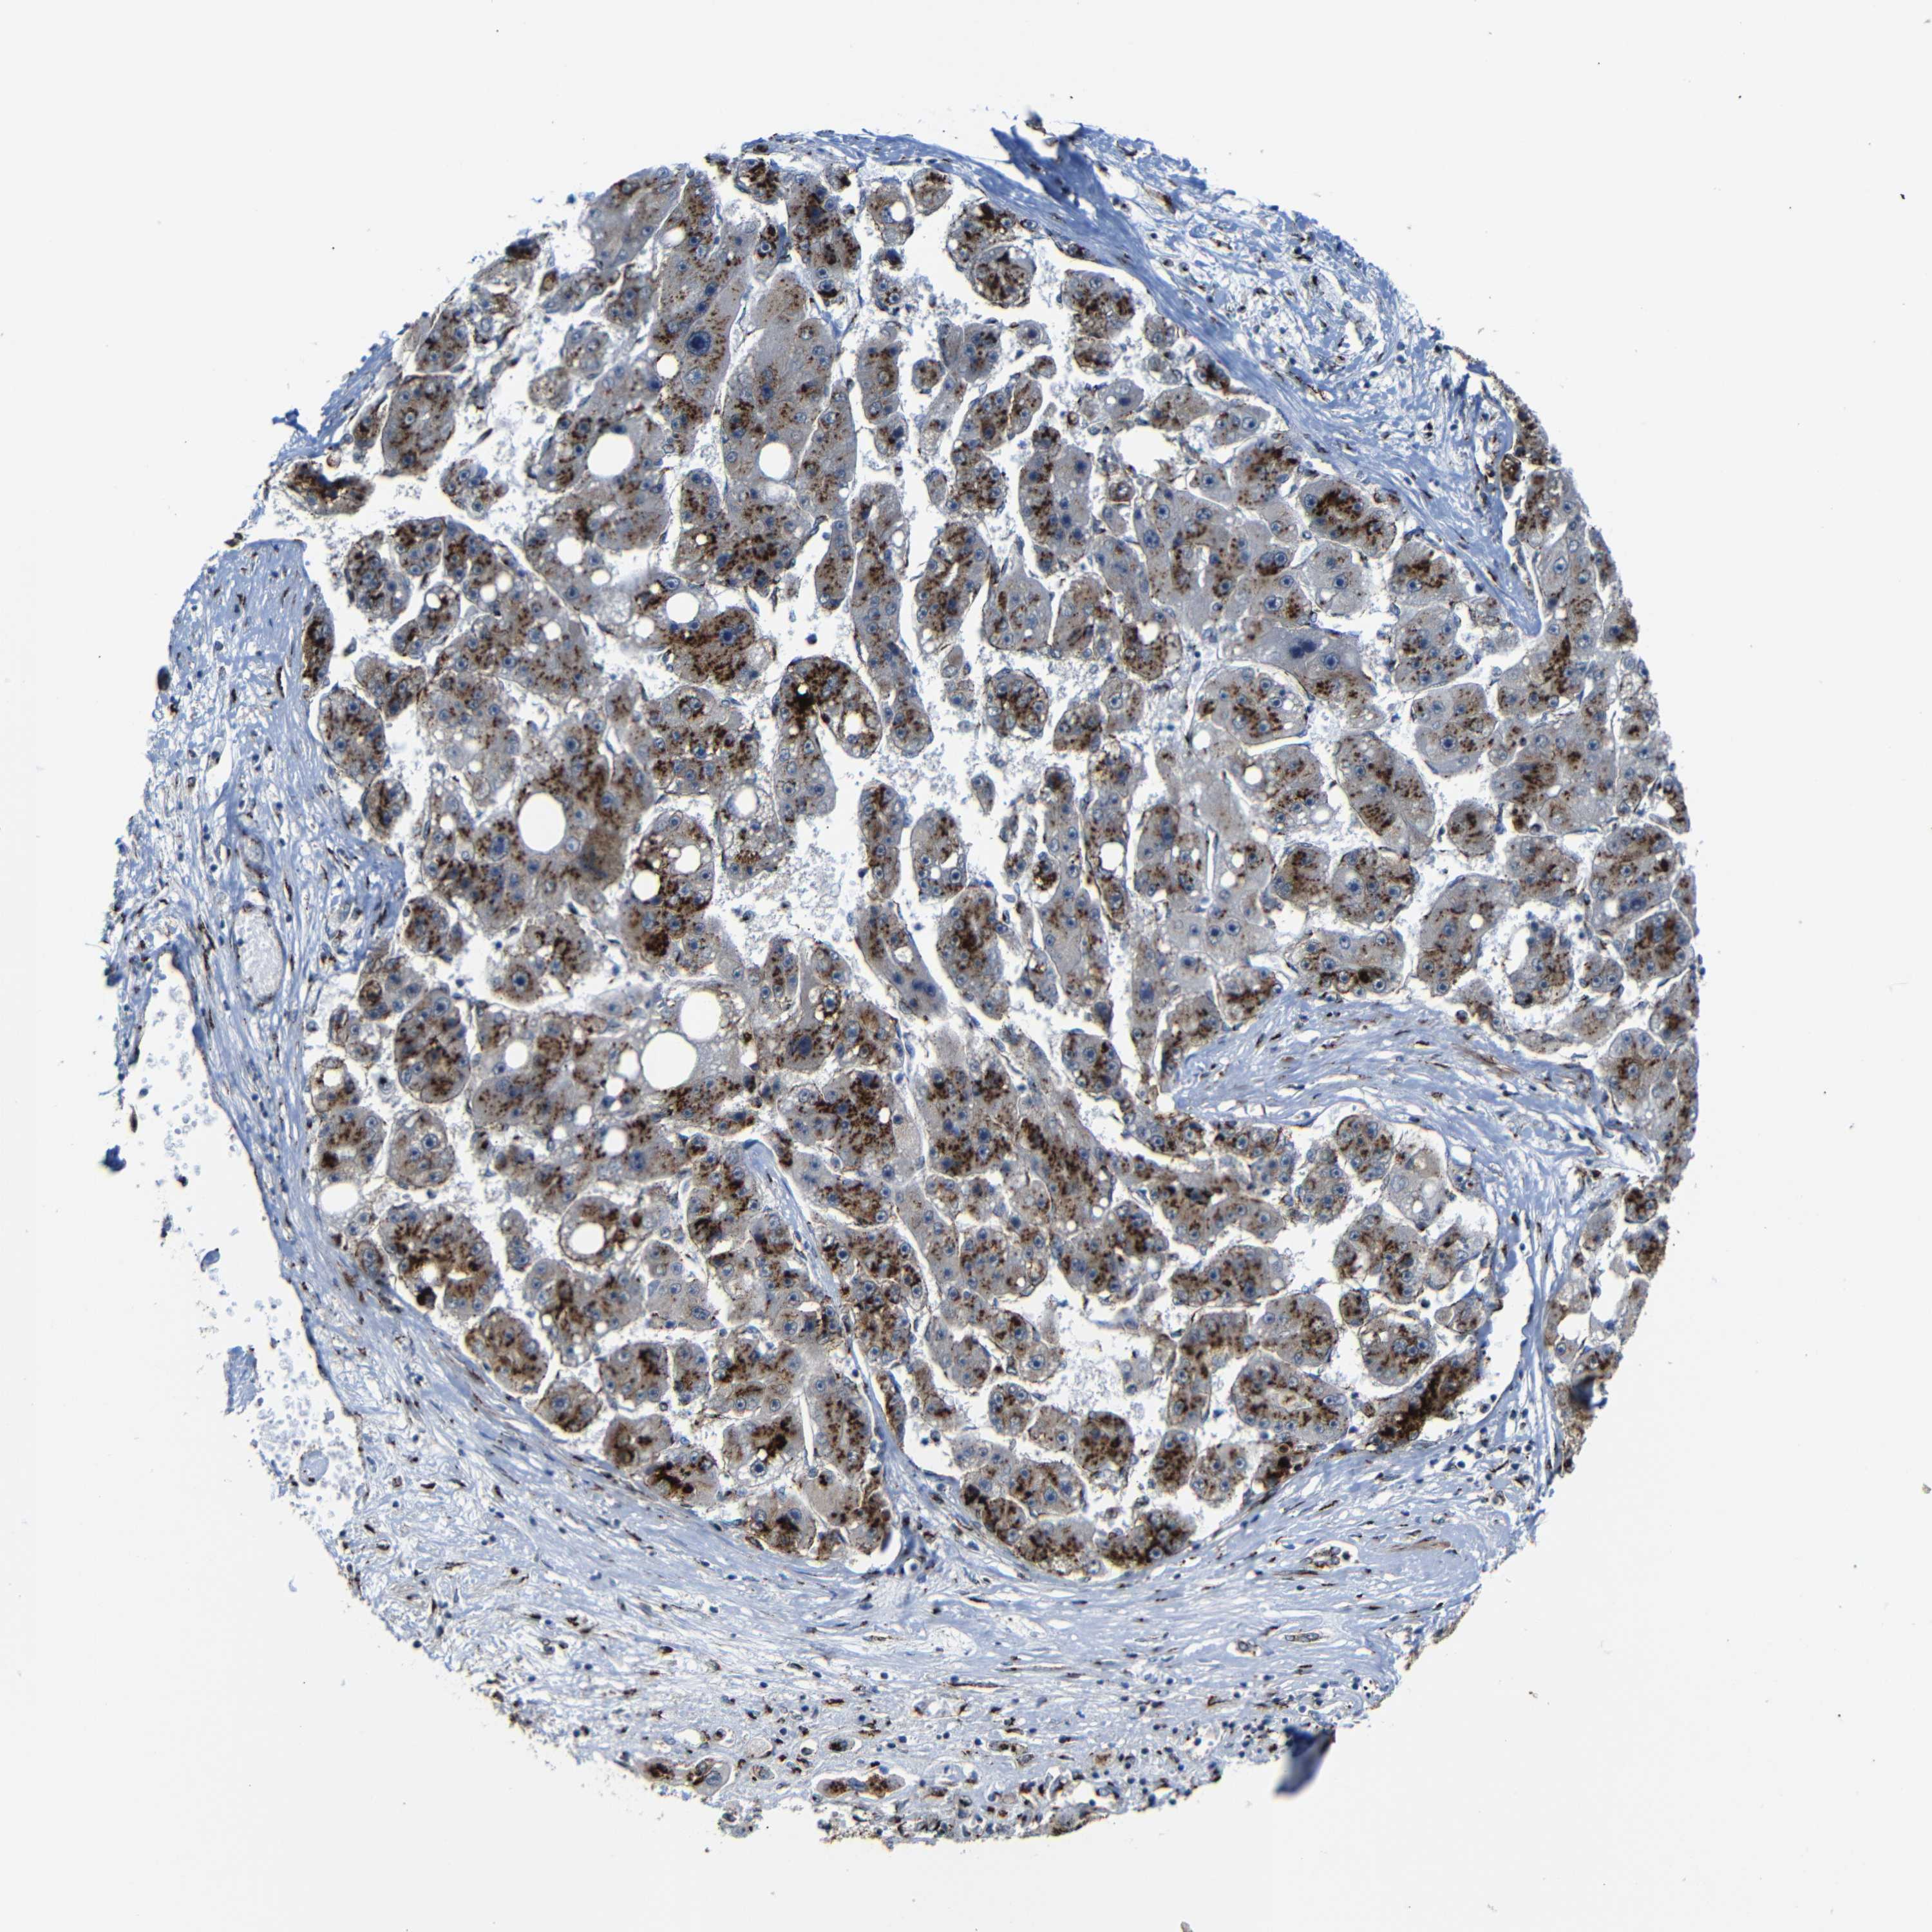

LIVER CANCER - Protein expressioni

A mouse-over function shows sample information and annotation data. Click on an image to view it in a full screen mode. Samples can be filtered based on level of antibody staining by selecting one or several of the following categories: high, medium, low and not detected. The assay and annotation is described here.

Antibody stainingi

Antibody staining in the annotated cell types in the current human tissue is reported as not detected, low, medium, or high, based on conventional immunohistochemistry profiling in selected tissues. This score is based on the combination of the staining intensity and fraction of stained cells.

Each image is clickable and will lead to virtual microscopy that enables deeper exploration of all samples and also displays staining intensity scores, fraction scores and subcellular localization as well as patient and tissue information for each sample.

Antibody HPA012609

Antibody HPA012723

Antibody CAB011489

Staining

High

Medium

Low

Not detected

Intensity

Strong

Moderate

Weak

Negative

Quantity

>75%

75%-25%

<25%

None

Location

Nuclear

Cytoplasmic/membranous

Cytoplasmic/membranous,nuclear

Cholangiocarcinoma

Carcinoma, Hepatocellular, NOS